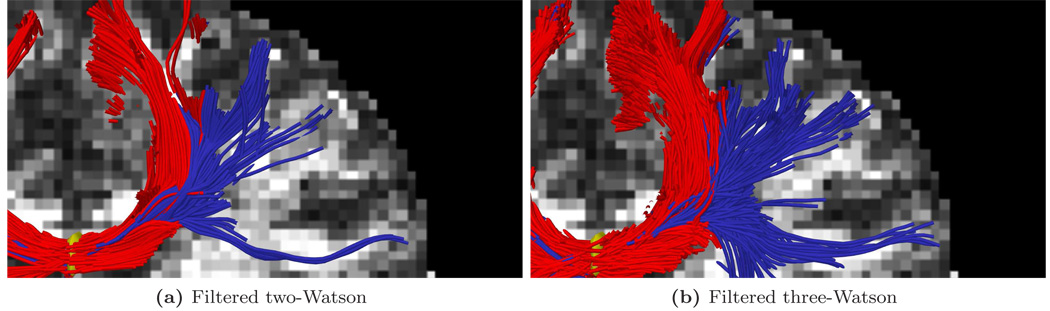

Figure 10.

Closeup of upper right in Fig. 9c and Fig. 9d.

For the first experiment, Fig. 9 shows tracts originating from within a few voxels intersecting a particular coronal slice. For a reference backdrop, we use a coronal slice showing the intensity of fractional anisotropy (FA) placed a few voxels behind the seeded coronal position. Keeping in mind that these fibers are intersecting or are in front of the image plane, this roughly shows how the fibers navigate the areas of high anisotropy (bright regions). Similar to the results in [17, 46], Fig. 9b shows that sharpened spherical harmonics only pick up a few fibers intersecting the U-shaped callosal radiata. In contrast, our proposed method traces out many pathways consistent with the apparent anatomy using either the two-fiber or three-fiber model. To emphasize transcallosal tracts, we color as blue those fibers exiting a corridor of ±22 mm around the mid-sagittal plane. Fig. 10 provides a closer inspection of Fig. 9c and Fig. 9d where, to emphasize the underlying anatomy influencing the fibers, we use as a backdrop the actual coronal slice passing through the voxels used to seed this run. Such results are obtained in minutes in our current Matlab implementation. At each step, the cost of reconstructing the signal for few sigma points approaches the cost of a few iterations of weighted least-squares estimation of a single tensor.